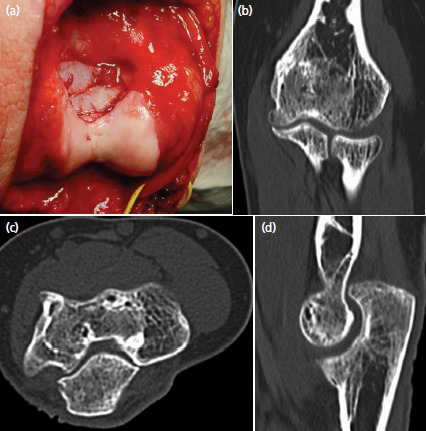

A 19-year-old, healthy women without previous medial problems consulted her general practitioner because of pain and decreased range of motion in her left elbow for six months. Standard radiographs showed a lytic lesion in the trochlea. She was referred to us for further assessment and treatment. The posteromedial aspect of the elbow was slightly swollen and sensitive to pressure. Skin temperature and colour were normal. Flexion was restricted to 100°, the extension deficit was 40°. Pronation and supination and peripheral sensibility and motor function were normal. Additional magnetic resonance images and computed tomography scans of the elbow revealed a locally destructive tumour in the distal humerus, involving almost the whole trochlea (Fig. 1). The cortical bone adjacent to the olecranon fossa was perforated and the tumour penetrated into the posterior compartment of the joint. It expanded proximally under the triceps but did not infiltrate this muscle. An open biopsy was performed, and the histologic analysis of tissue samples confirmed the diagnosis of a giant cell tumour. A CT thorax and scintigraphy of the skeleton showed no other lesions, especially lung metastases.

Fig. 1.

Pre- and intra-operative images revealing the big lytic lesion in the epiphysis of the left elbow: (a) anteroposterior radiograph, (b) coronal, (c) axial and (d) sagittal CT-images, (e) sagittal MRI, and (f) posterior view after intralesional curettage and high-speed burring. The subchondral bone of the trochlea and the medial epicondyle was severely thinned out and posteriorly disrupted. The ulnar nerve was marked with a vessel loop.